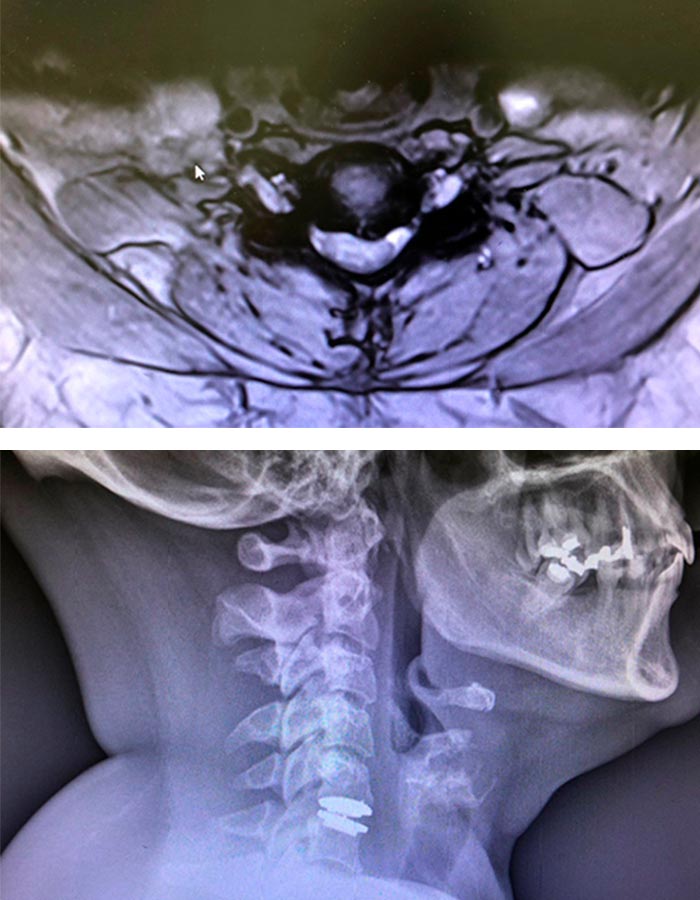

Preoperatorio

Este dolor le condicina al paciente una pérdida de fuerza en el brazo izquierdo así como dolor intenso por el brazo y hombro. Tras tratamiento médico y rehabilitador sin éxito, comento a la paciente que requiere una cirugía mínimamente invasiva para solucionarle el problema.

Hernia discal cirugia

Hernia discal cuello

Operación

Procedemos a realizar una cirugía donde retiramos la hernia y le colocamos un disco completamente móvil, a través de una incisión de 2 cm a nivel de la piel.